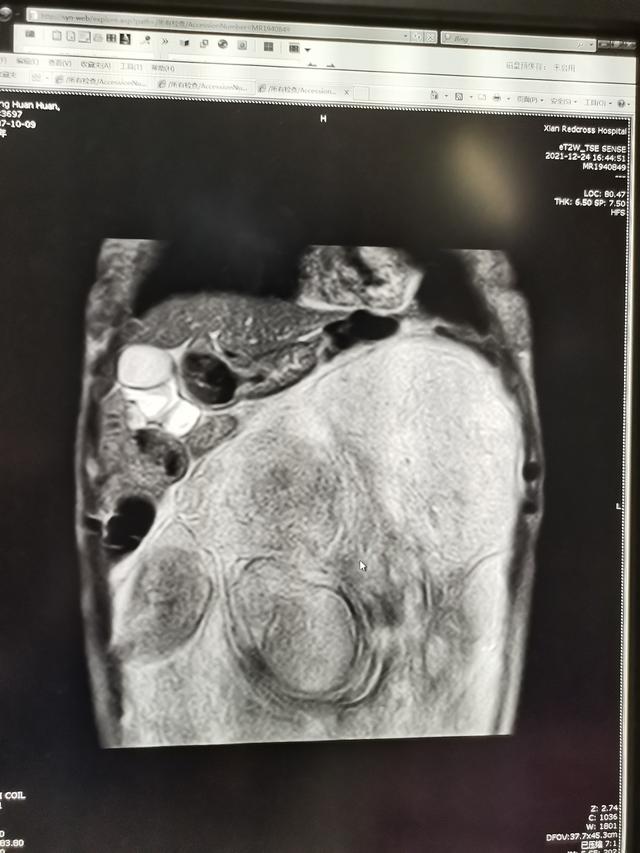

肿块占据大部分腹腔

患者入院检查时发现,下腹部可见一巨大肿块,大小约30cmx30cm。CT中可看到肿块几乎占据大部分腹腔,与腹腔内重要内脏和大血管粘连紧密,而且左侧肾脏已经被推移至右上腹。孙力主任组织全科人员进行了病情讨论,认为腹部肿物切除是唯一的解决方案。但瘤体巨大,周围解剖关系复杂,稍有不慎可能损伤周围重要脏器及大血管,导致难以控制的大出血,甚至死亡,手术难度极大,风险极高。在邀请院内多个科室进行会诊,在充分沟通交流后,制订了详尽的手术方案。